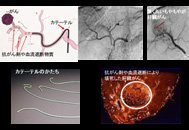

肝臓がんのカテーテル検査

肝臓がんは血流豊富ながんである

~がんを焼く・固める治療です - カテーテル治療

~カテーテルでがんのあるところまで行き、抗がん剤を流したり、がんにいく血流を遮断(いわゆる兵糧攻め)する治療。

~多くの病院が足からカテーテル検査治療するのに対し当院では手から検査・治療を行います。足からに比べアンケート結果から楽なことが特徴です。 - 内服治療

肝臓がんのカテーテル治療